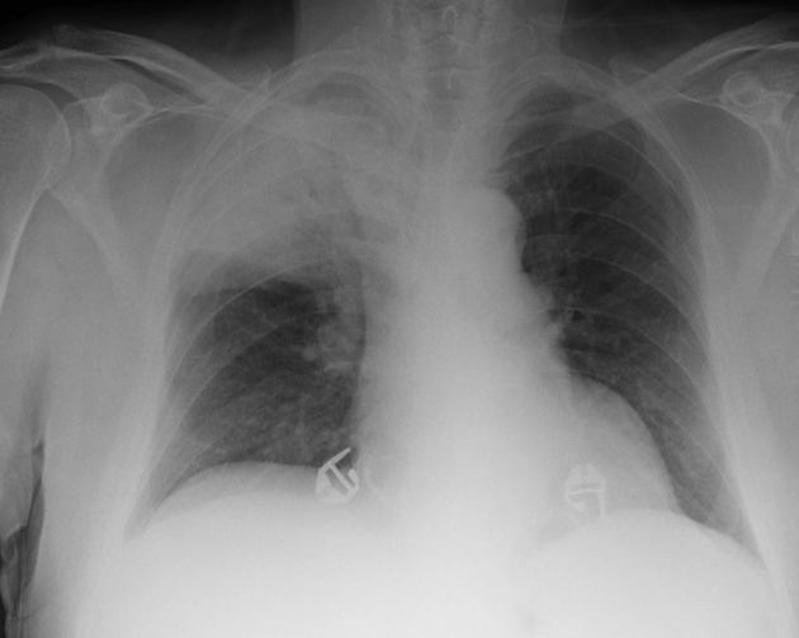

Về triệu chứng lâm sàng, bệnh thường khởi phát đột ngột với sốt cao, rét run, đau ngực kiểu màng phổi và ho. Người bệnh có thể ho ra đờm đặc, đôi khi có màu gỉ sắt do chứa hồng cầu. Khám lâm sàng có thể phát hiện các dấu hiệu đông đặc phổi như rung thanh tăng, gõ đục và nghe phổi có ran nổ. Trên X-quang ngực, viêm phổi thùy thường biểu hiện bằng hình ảnh đông đặc đồng nhất của một thùy phổi – là dấu hiệu khá đặc trưng giúp hỗ trợ chẩn đoán [2].

Khi quá trình viêm lan rộng và dịch viêm tích tụ ngày càng nhiều, nhu mô phổi trong thùy bị tổn thương sẽ trở nên đông đặc. Trên lâm sàng và hình ảnh học, vùng phổi này mất tính chứa khí và trở nên đặc giống mô gan, hiện tượng này thường được gọi là “gan hóa phổi” [5]. Chính sự đông đặc toàn bộ một thùy phổi này tạo nên hình ảnh điển hình và đặc trưng của viêm phổi thùy trên X-quang ngực cũng như trong giải phẫu bệnh.

Việc nhận biết sớm các dấu hiệu lâm sàng kết hợp với chẩn đoán hình ảnh (đặc biệt là X-quang ngực với hình ảnh đông đặc thùy điển hình) có ý nghĩa rất quan trọng trong thực hành lâm sàng. Điều trị kịp thời bằng kháng sinh phù hợp không chỉ giúp kiểm soát nhiễm trùng mà còn ngăn ngừa các biến chứng nặng như tràn dịch màng phổi, áp xe phổi hoặc suy hô hấp, từ đó cải thiện rõ rệt tiên lượng và giảm tỷ lệ tử vong cho người bệnh.